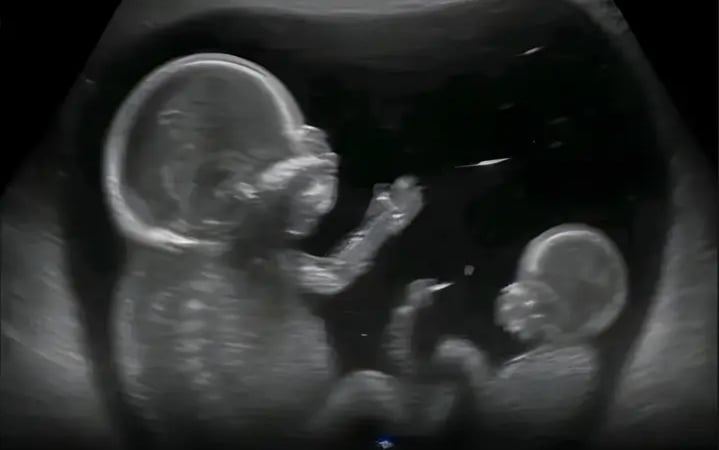

މިއީ އާދައިގެ މަތިން އިންސާނާގެ ހަށިގަނޑުގައި ކަން ހިނގާ އުސޫލާ މުޅިން ޚިލާފު، ސައިންސްވެރިންނާއި ޑޮކްޓަރުން ހައިރާންކޮށްލާފަދަ ނާދިރު ކަމެކެވެ. "ސުޕަފިޓޭޝަން" ގެ ނަމުން ނަންދެވިފައިވާ މި ހާދިސާއަކީ އަންހެނަކު ބަނޑުބޮޑުވެފައި ވަނިކޮށް، ދެވަނަ ފަހަރަށް ބިސް ދޫކޮށް، އެ ބިސް ފާޓިލައިޒްވެ، އަލުން ބަނޑުބޮޑުވުމެވެ. މިކަމުގެ ސަބަބުން އެއް ރަހިމެއްގެ ތެރޭގައި ތަފާތު ދެ އުމުރެއްގެ ދެ ކުދިން ބޮޑުވަމުންދެއެވެ.

އާންމުގޮތެއްގައި އަންހެނަކު ބަނޑުބޮޑުވުމުން، ހަށިގަނޑުން ބޭރުކުރާ ހޯރމޯންތަކުގެ ސަބަބުން އިތުރު ބިސް ދޫކުރުން ހުއްޓުވައިދެއެވެ. ނަމަވެސް "ސުޕަފިޓޭޝަން" މެދުވެރިވާ ހާލަތުގައި ހަށިގަނޑުގެ މި ގުދުރަތީ ނިޒާމަށް ބަދަލު އައިސް، ބަނޑުގައި ކުއްޖަކު އޮއްވައި އިތުރު ބިހެއް ދޫކުރަނީއެވެ. އަދި އެ ބިސް ރަހިމުގެ ފާރުގައި ހަރުލައި، ދެވަނަ ފަނިލަފެއްގެ ގޮތުގައި އާލާވާން ފަށަނީއެވެ. މިކަމުގެ ސަބަބުން މި ދެ ކުދިންގެ އުމުރުގައި ދުވަސްތަކެއް ނުވަތަ ހަފުތާތަކެއްގެ ތަފާތު ހުރެއެވެ. މިއީ އެއްމާބަނޑު ދެކުދިންނާ ޚިލާފަށް، ދެ ދުވަސްވަރެއްގައި އުފެދޭ ދެ މާބަނޑުވުމެއް އެއްފަހަރާ ހިނގުމެވެ.

މި ހާދިސާގައި ދެ ކުދިންގެ އުމުރު ތަފާތުވި ނަމަވެސް، ގިނަ ފަހަރަށް މި ދެ ކުދިން ވިހަނީ އެއް ދުވަހެއްގައެވެ. މީގެ މާނައަކީ ފަހުން އުފެދުނު ކުއްޖާ ދުވަސް ނުފުރާ ވިހެއުމުގެ ފުރުސަތު ބޮޑުވުމެވެ. ސިއްހީ މާހިރުން ވިދާޅުވާ ގޮތުގައި މިއީ އިންސާނާގެ ބިޮލޮޖިކަލް ނިޒާމުން ފެންނަ އެންމެ އާދަޔާޚިލާފު އެއް ކަންތަކެވެ. ސަބަބަކީ ބަނޑުބޮޑުވުމަށްފަހު ރަހިމުގެ ދޮރު ބަންދުވެ، އިތުރު ދަރިމައިވުމަކަށް ހަށިގަނޑު ހުރަސްއަޅާ ހުރަސްތައް މި ހާލަތުގައި މުގުރާލާތީއެވެ.